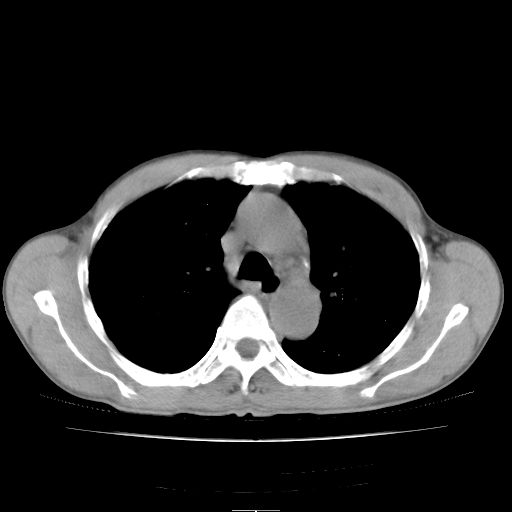

标题: CT25795:感冒后反复咳嗽两月余,痰中带血半月余。X诊断“肺 [打印本页]

标题: CT25795:感冒后反复咳嗽两月余,痰中带血半月余。X诊断“肺

1.双肺肺梗塞(理由:病灶呈三角形,与胸膜相连且局部胸膜肥厚,左心室增大)伴肺感染。

2.一元论双肺感染。